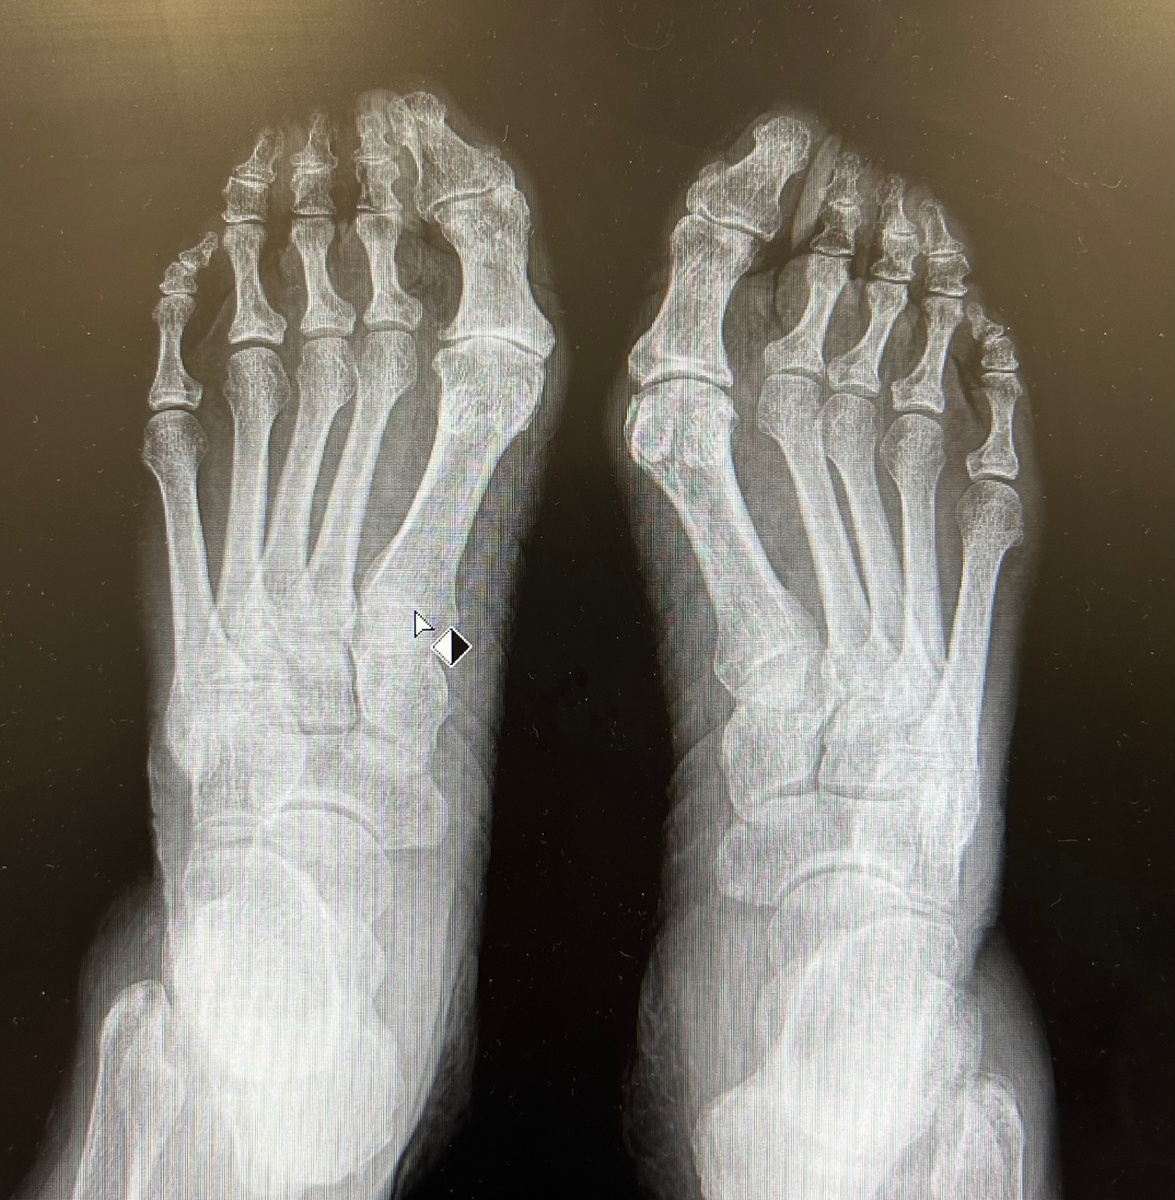

Рентген стопы до операции(хоть на правой ноге деформации выраженней, но на левой ноге явно выражен артроз сустава, который приносит боль)